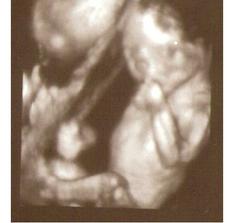

7.11. jsme byly na 3D UTZ, kluci sebou mleli o stošest a jeden bude nejspíš celý tatínek 😀, neb když došlo na focení, tak si dal ruku před obličej a že se prý neukáže 🙂)))